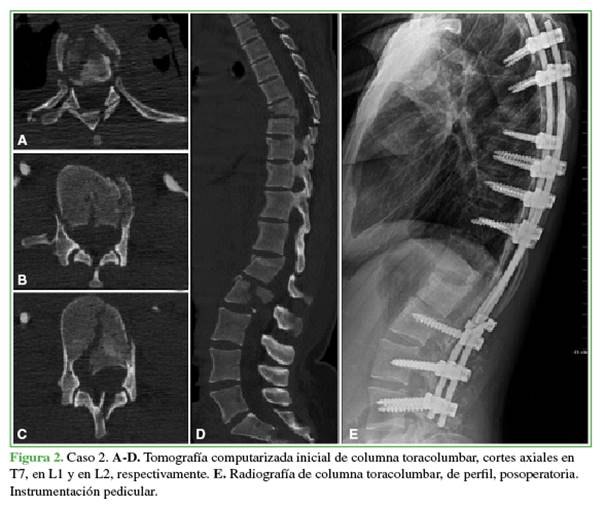

Durante el período de estudio, hubo cinco pacientes (1 mujer y 4 hombres) con dos fracturas vertebrales inestables simultáneas, con cuatro casos (80%) de fracturas no contiguas. De acuerdo con el tipo de fracturas asociadas, tres (60%) tenían dos luxofracturas (AOSpine: tipo C) simultáneas no contiguas, asociación denominada columna flotante, según publicaciones previas. Como variante de lesión, dos (40%) pacientes tenían la asociación de una fractura tipo B con una tipo C. La mediana de la edad era de 35 años (rango 23-49). Todos habían sufrido traumatismos de alta energía (3 accidentes de tránsito, 2 caídas de gran altura) con lesiones asociadas. Predominó el traumatismo grave de tórax con fracturas costales y hemotórax (n = 3, 60%). Se registraron escasas comorbilidades previas: un paciente con antecedente de depresión mayor e intento autolítico y uno con osificación del ligamento longitudinal posterior cervical. En la Tabla 1, se resume la descripción de la muestra y, en la Tabla 2, se describen los casos (Figuras 1-4).